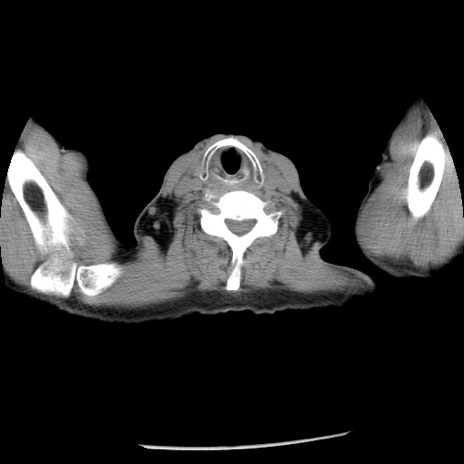

症例26(横断像)

【症例】80歳代男性

【主訴】嘔吐

【現病歴】昨晩2回嘔吐あり、今朝になっても嘔吐あり。来院。

【既往歴】胃潰瘍

【身体所見】意識清明、BT 37.6℃、BP 166/95mmHg、HR 100bpm、SpO2 97%、腹部:平坦・軟、腸蠕動音聴取良好、圧痛なし。

【データ】WBC 21900、CRP 1.46